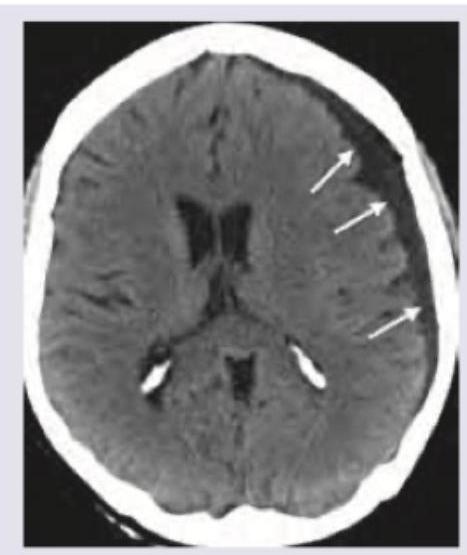

Question 18: Which is correct about the intracranial bleeding shown below?

- A. Chronic subdural hematoma, hypodensity (Correct Answer)

Explanation: ***Chronic subdural hematoma, hypodensity*** - The image displays a crescent-shaped collection of fluid with **hypodense characteristics** (darker than brain parenchyma) that crosses suture lines, which is typical for a subdural hematoma. - The **hypodensity indicates older, chronic blood** where the hemoglobin has degraded, differentiating it from acute (hyperdense) or subacute (isodense) collections. *Acute subdural hematoma, hypodensity* - An **acute subdural hematoma** would typically appear **hyperdense** (bright) on CT due to fresh blood. - The observed collection is clearly hypodense, ruling out an acute presentation. *Chronic epidural hematoma, hyperdensity* - An **epidural hematoma** is typically **lenticular (lens-shaped)** and does not cross suture lines, unlike the crescent shape seen here. - While chronic blood *can* be hypodense, an epidural hematoma by definition is outside the dura mater and would not present with this morphology. *Acute epidural hematoma, hyperdensity* - An **acute epidural hematoma** is characterized by a **lenticular (lens-shaped) hyperdense** collection of blood, which is distinctly different from the crescent-shaped, hypodense collection in the image. - Epidural hematomas occur between the dura mater and the skull, typically from arterial injury, and are bound by sutures.